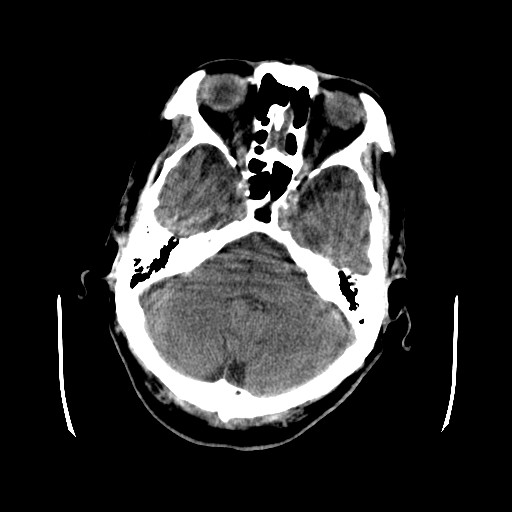

患者,男,70岁,清晨(10小时前)无法自行起床,家人无法唤醒,现昏迷,大小便失禁

肿快呈以等密度为主的等高密度影,占位效应不是很明显,只是左枕角受压,肿块内侧似有低密度改变.

单纯出血吸收应该从周边开始,

左颞枕叶交界区可见类圆形高密度区,边缘可见环形更高密度影,侧脑室后角明显受压而周围未见明显水肿.考虑脑膜瘤伴出血可能性大不排外血管畸形.建议mr进一步检查.

左颞枕叶交界区的类圆形高密度区首先考虑脑膜瘤卒中,病人左侧小脑半球的还有多个囊性低密度,要考虑同时伴有梗塞的可能。

这个病人做ct时已经10小小时了,按说出血多稳定了,这么少的出血和这么小、少的梗塞怎么会导致病人昏迷?而脑干、脑桥和中脑都没有发现出血或梗塞,也没有明显的颅内高压,真的很奇怪。